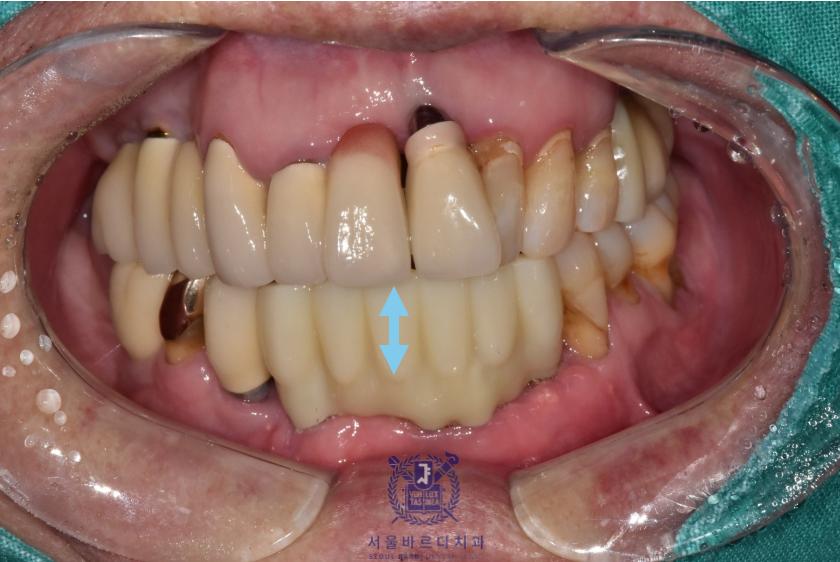

왼쪽 위 역시 가장 이상적인 위치에 성공적으로 임플란트를 식립하였습니다.

다행히 수술 후 지혈도 잘 되시고 회복하는 과정에도

환자분이 지시에 잘 따라주셔서 잇몸도 예쁘게 아물었습니다.

환자분마다 차이가 있지만 통상적으로

3~6개월간 임플란트가 뼈에 단단하게 굳는 기간을 가진 후

보철을 준비하게 됩니다.

아래 앞니는 6개의 치아를 안정적으로 유지할 수 있는

견고한 4개의 뿌리를 식립하였고

왼쪽 위는 큰어금니 다음으로 중요한 역할을 수행할 작은

어금니에 맞는 사이즈로 식립하였습니다.

초기 고정이 잘 나와 임플란트가 단단하게 잘 굳었고,

성공적으로 보철까지 잘 마무리 해드렸습니다.

앞으로 새로 할 보철은 깨끗한 색이였으면 한다고 하셔서

앞니는 조금 밝은 색으로 진행하게 되었습니다.

아래 컬러에 맞춰 기존에 있는 보철들도 추후 차례대로 교체하기로하셨습니다.

앞니는 기능적이면도 있지만 심미적인 측면이 매우 중요하기 때문에

최대한 환자분에게 적합한 형태로

환자분의 의견을 적극 반영하여 제작하고 있습니다.

이전의 브릿지 보철은 공간을 꽉 채우는 느낌으로 제작되어

이가 너무 길어보이는 느낌이 있어

이번에는 볼륨을 통해 치아가 길어보이지 않게 제작했습니다.

실제로 치아가 보이는 부분은 이 앞의 보철과는 다르게

짧게 표현되어 환자분이 아주 만족스러워하셨습니다.